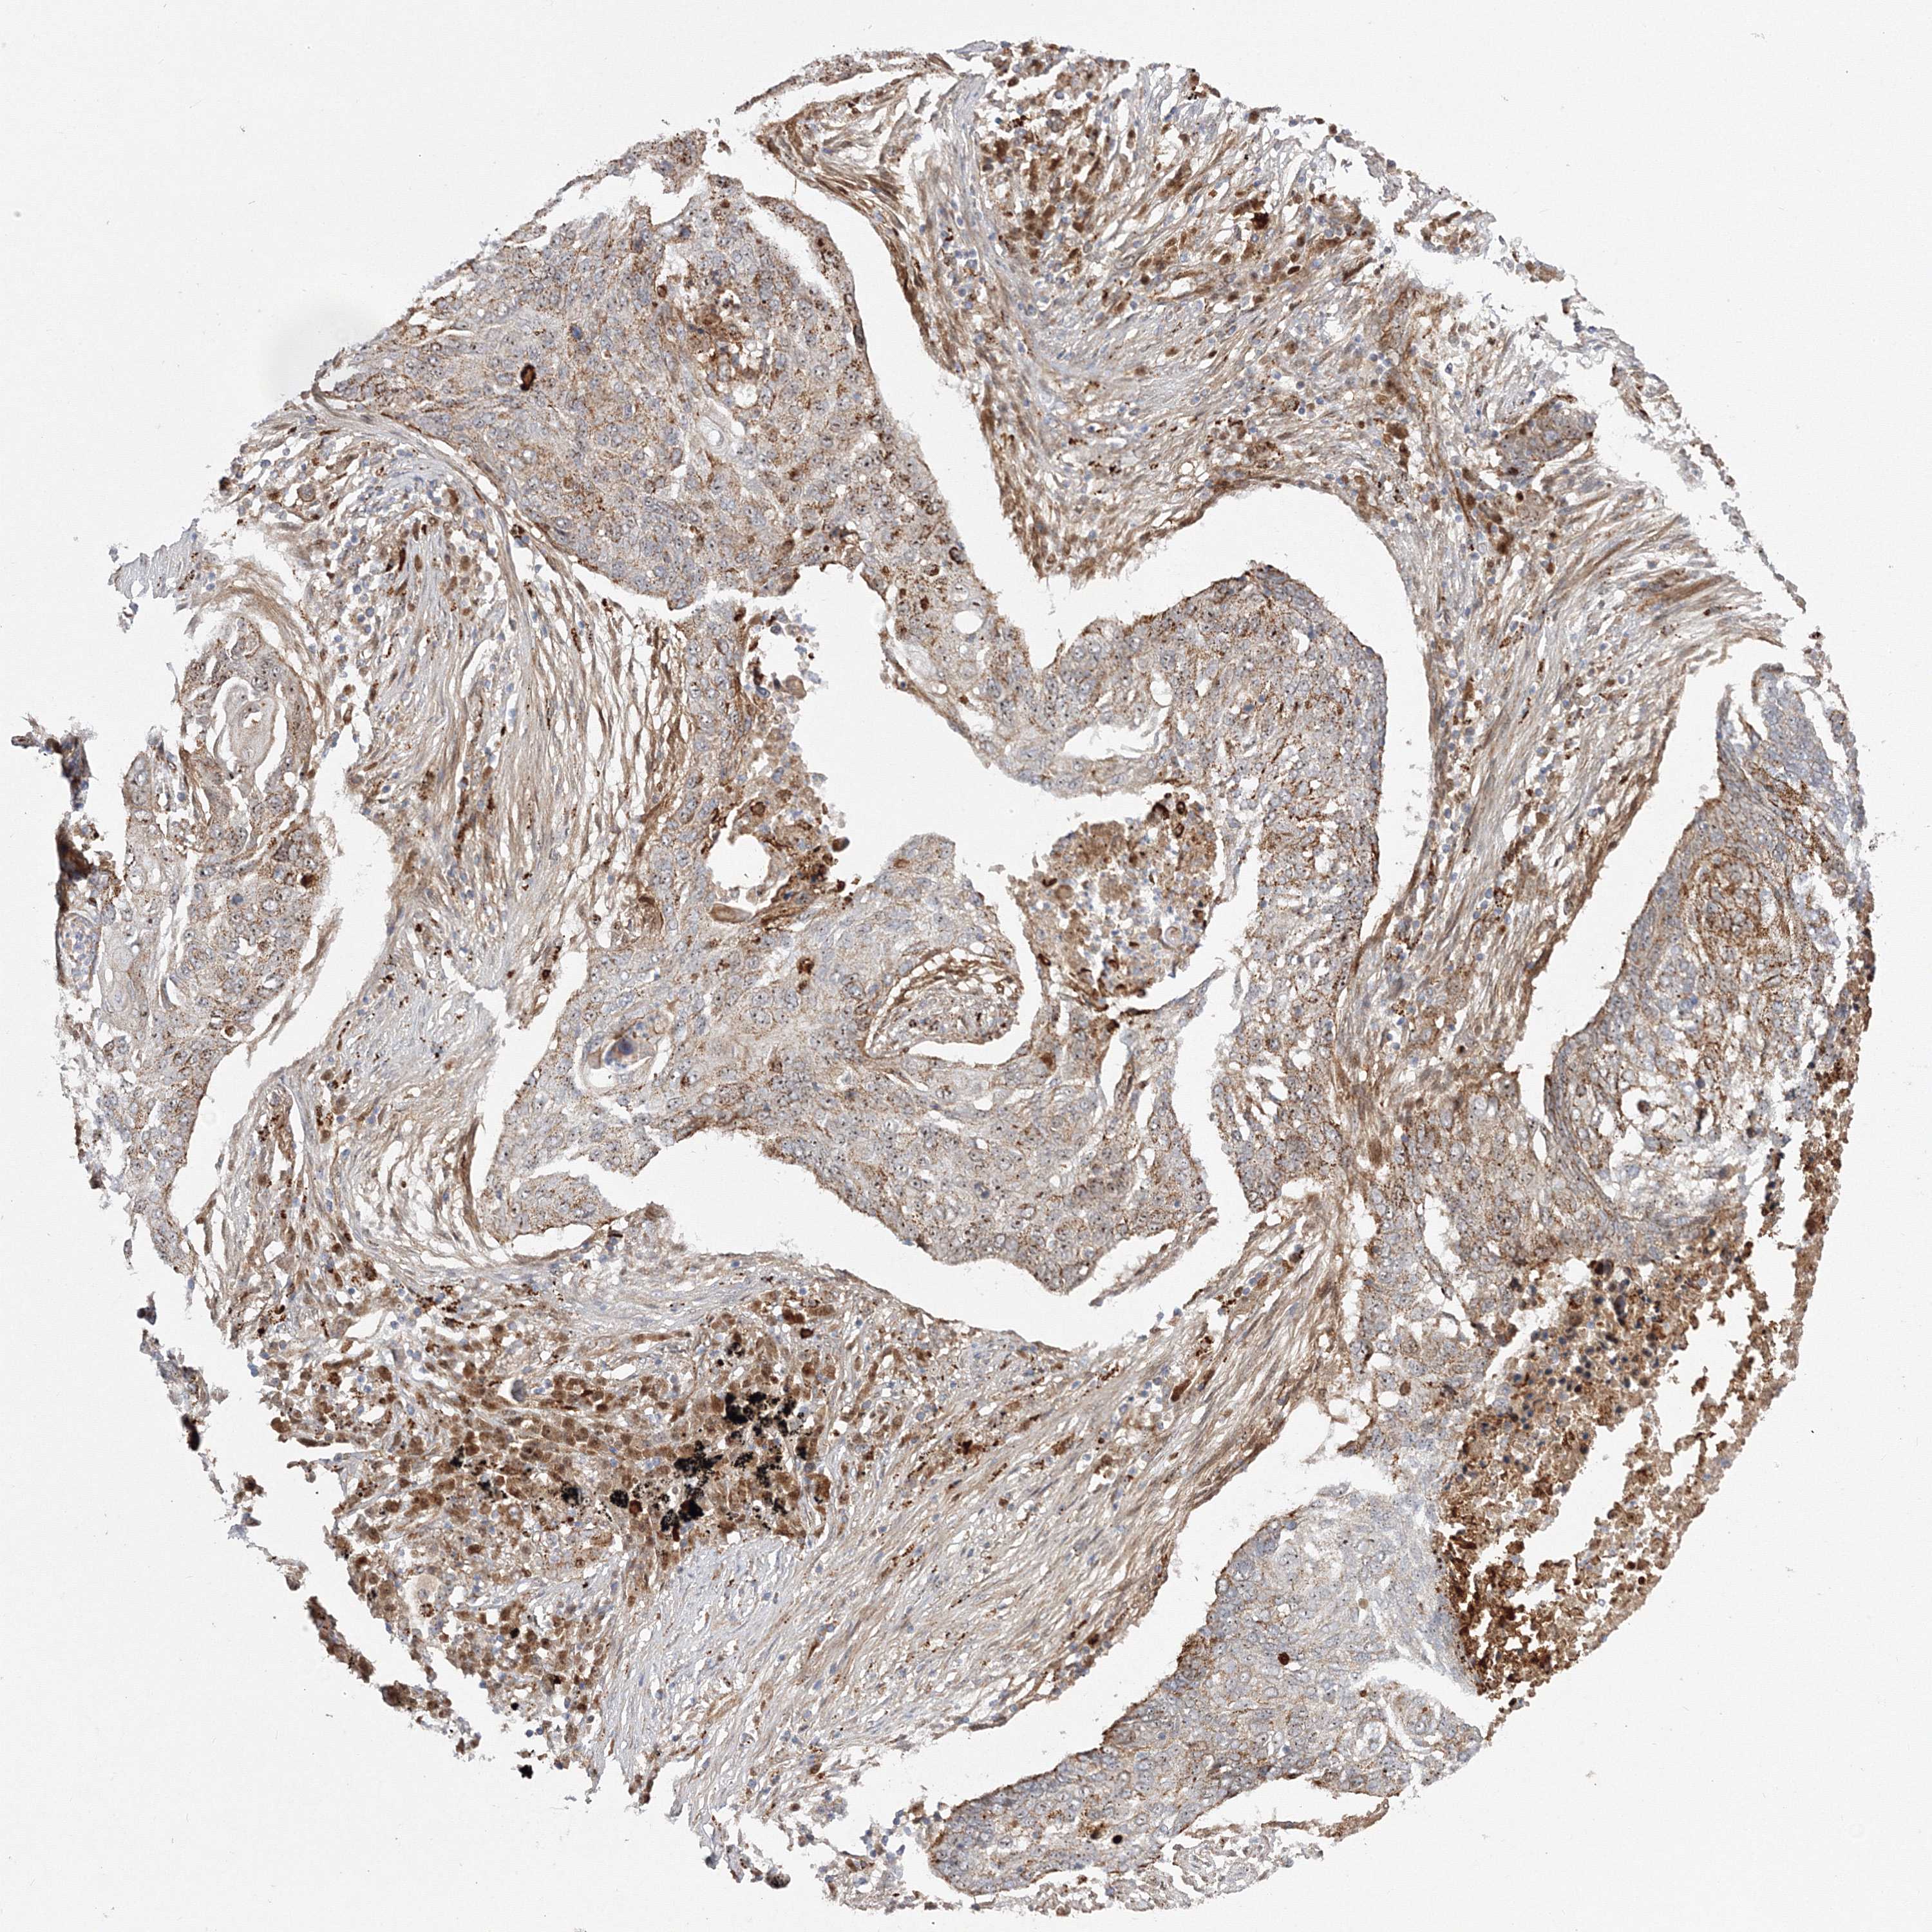

LUNG SQUAMOUS CELL CARCINOMA (TCGA) - Interactive survival scatter ploti

The Survival Scatter plot shows the clinical status (i.e. dead or alive) for all individuals in the patient cohort, based on the same data that underlies the corresponding Kaplan-Meier plots. Patients that are alive at last time for follow-up are shown in blue and patients who have died during the study are shown in red.

The x-axis shows the expression levels (FPKM) of the investigated gene in the tumor tissue at the time of diagnosis. The y-axis shows the follow-up time after diagnosis (years). Both axes are complimented with kernel density curves demonstrating the data density over the axes. The top density plot shows the expression levels (FPKM) distribution among dead (red) and alive patients (blue). The right density plot shows the data density of the survived years of dead patients with high and low expression levels respectively, stratified using the cutoff indicated by the vertical dashed line through the Survival Scatter plot. This cutoff is automatically defined based on the FPKM cutoff that minimizes the p-score. The cutoff can be changed by dragging the vertical line or by entering a cutoff value in the square labeled "Current cut-off".

Under the Survival Scatter plot the p-score landscape (black curve; left axis) is shown together with dead median separation (red curve; right axis). Dead median separation is the difference in median mRNA expression between patients who have died with high and low expression, respectively. It is calculated as follows: median FPKM expression of dead patients with high expression - median FPKM expression of dead patients with low expression. This is intended to aid the user in visually exploring custom cutoffs and the associated p-scores and dead median separation.

Individual patient data is displayed and can be filtered by clicking on one or more of the category buttons on the top of the page. Categories describing expression level and patient information include: high, low, alive, dead, female, male and tumor stages. The scale of the x-axis can be toggled between linear and log-scale by clicking on the "x log" button. Mouse-over function shows TCGA ID, patient information and mRNA expression (FPKM) for each patient.

& Survival analysisi

Kaplan-Meier plots summarize results from analysis of correlation between mRNA expression level and patient survival. Patients were divided based on level of expression into one of the two groups "low" (under cut off) or "high" (over cut off). X-axis shows time for survival (years) and y-axis shows the probability of survival, where 1.0 corresponds to 100 percent.

NPM3 is not prognostic in Lung Squamous Cell Carcinoma (TCGA)

Stage:

Survival analysis

Current cut offi

Current cut-off shows the cut-off (FPKM) currently selected. It may be changed manually. When the current cut-off is changed, the vertical dashed line indicating cut-off, the interactive survival scatter plot and the Kaplan-Meier curve will be automatically adjusted to show results accordingly.

:

Best expression cut offi

Based on the FPKM value of each gene, patients were classified into two groups and association between prognosis (survival) and gene expression (FPKM) was examined. The best expression cut-off refers the FPKM value that yields maximal difference with regard to survival between the two groups at the lowest log-rank P-value. Best expression cut-off was selected based on survival analysis .

When clicking on this number, the vertical dashed line indicating cut-off, the interactive survival plot, and the Kaplan-Meier curve will be adjusted to show results based on the best expression cut-off.

: 41.4

Median expressioni

Median expression refers to the median FPKM value calculated based on the gene expression (FPKM) data from all patients in this dataset. When clicking on this number, the vertical dashed line indicating cut-off, the interactive survival plot, and the Kaplan-Meier curve will be adjusted to show results based on the median expression.

: N/A

Median follow up timei

Median follow up time refers to the median time (years) after diagnosis with this type of cancer, based on clinical data from all patients in this dataset.

P scorei

Log-rank P value for Kaplan-Meier plot showing results from analysis of correlation between mRNA expression level and patient survival.

N/A

5-year survival highi

5-year survival for patients with higher expression than the expression cutoff.

For melanoma and glioma, 3-year survival is shown.

5-year survival lowi

5-year survival for patients with lower expression than the expression cutoff.